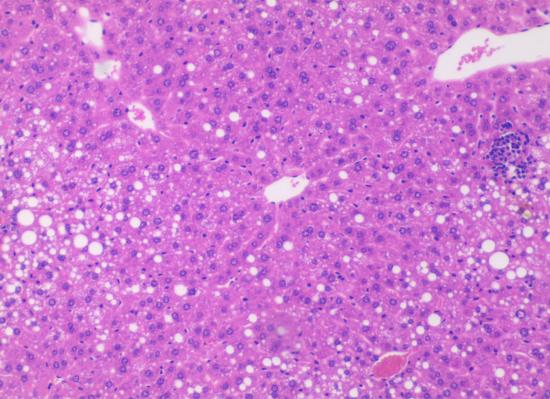

小鼠肝组织HE染色结果

图1

HE染色MCS饲料组(6周)

图2

HE染色MCD饲料组(6周)

图3

HE染色MRCD60饲料组

(6周)

图4

HE染色CD60饲料组

*注:

图1 小鼠肝脏组织肝小叶与汇管区结构正常,肝索排列整齐。正常肝组织肝索以中央静脉为中心,呈放射状排列,细胞形态清晰。

图2小鼠肝脏组织出现了大量的脂肪空泡,小鼠肝脏组织肝小叶与汇管区结构异常,肝索消失。

图3 MRCD60饮食引起小鼠出现肝脂肪变性及肝小叶炎性浸润。

图4 肝小叶结构紊乱、肝细胞胞浆内以小泡性脂肪病变为主。